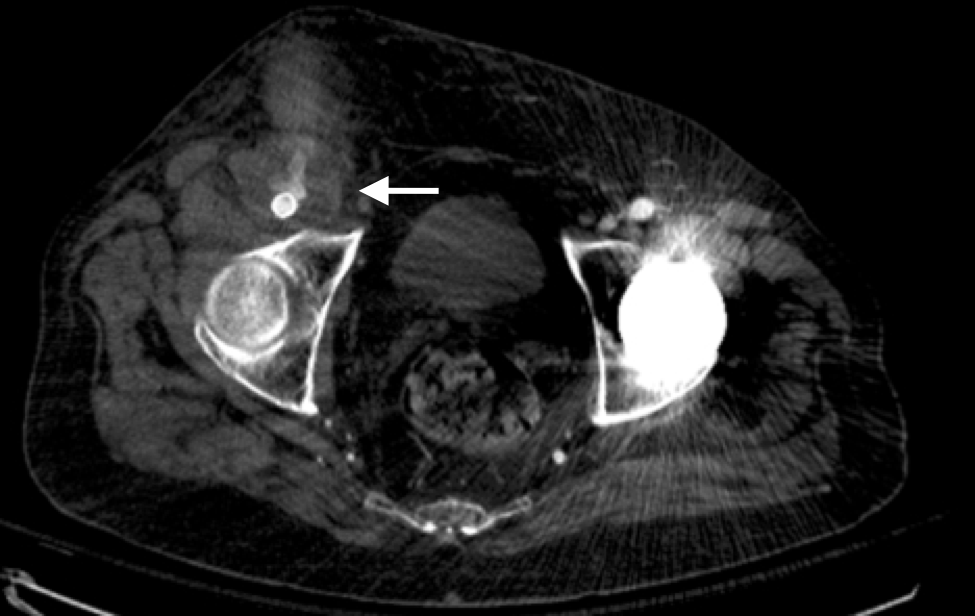

A surgeon from Nepal posted a case of a ruptured common femoral pseudoaneurysm infected from IV drug abuse on LinkedIn. The comments centered around typical textbook responses which were:

My preferred treatment is #2, in-situ bypass with harvest of adjacent deep femoral vein. I never liked that procedure because in general in these patients, everything bleeds. Then I had a thought -how about if you mobilize the external iliac artery in the pelvis over its entire length and pull it out from under the inguinal ligament to sew to the femoral bifurcation or SFA? That is, when you enter the pelvic retroperitoneum to gain proximal control:

You mobilize the external iliac artery from the iliac bifurcation to the inguinal ligament, detaching the inferior epigastrics as a last step. And then you pull it out from under the inguinal ligament, and anastomose it to the femoral bifurcation or the SFA.

This makes sense because in young people and those with AAA and minimal atherosclerosis, the external iliac artery is both redundant and elastic, making it suitable for a pull down transposition. But then, how do you know as you mobilize the artery in the pelvis that you have enough to pull down?